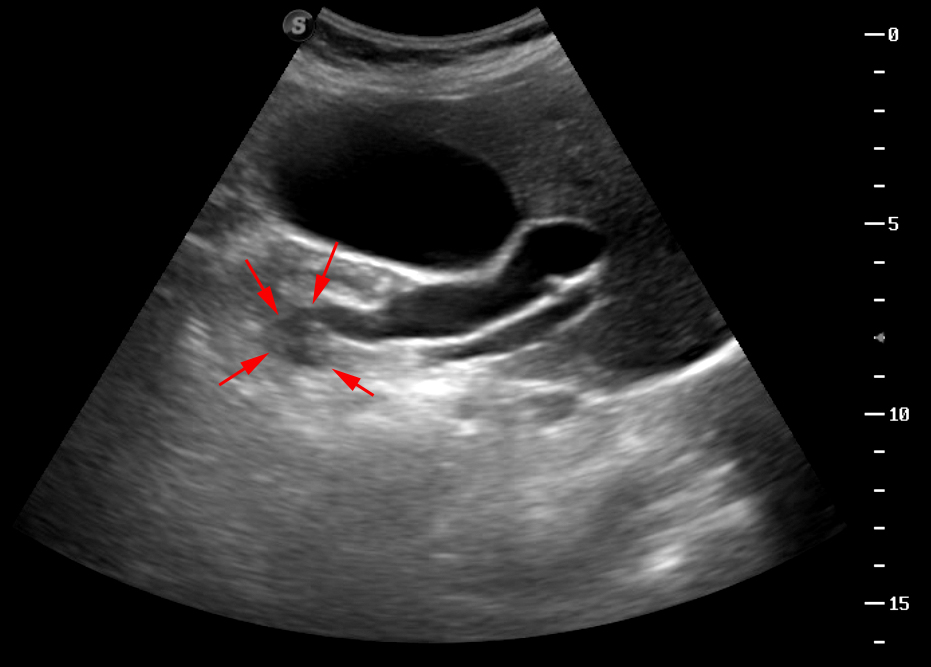

Опухоль головки панкреас - работа над ошибками

Пожилая женщина, без особых жалоб.

Сразу скажу, что опухоль я позорно просмотрел, хотя выявил признаки билиарной гипертензии.

Пересмотрите еще раз второй клип - вот как могут выглядеть признаки начальной панкреатической гипертензии.